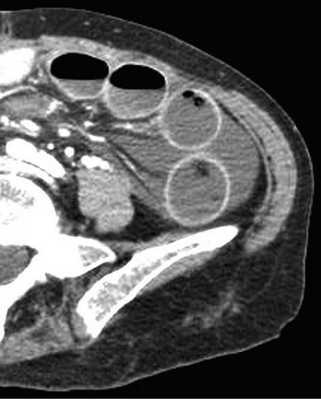

(Слева) На аксиальной КТ с контрастным усилением, выполненной мужчине 27 лет, у которого появилась боль и рвота, определяется, что тонкая кишка целиком, включая двенадцатиперстную кишку, располагается справа от средней линии. Слепая кишка расположена центрально, а ободочная кишка — справа от средней линии.

(Справа) На рентгенограмме, полученной при рентгеноскопии верхних отделов ЖКТ у этого же пациента, определяется частичная обструкция на уровне дистальных отделов двенадцатиперстной кишки, которая не пересекает среднюю линию, но имеет своеобразный вид, напоминающий букву Z или «штопор». На операции подтвердилась мальротация и обструкция двенадцатиперстной кишки, обусловленная тяжами (Ледда).

• Верхняя брыжеечная вена (ВБВ) занимает более вентральное положение либо находится слева от верхней брыжеечной артерии (ВБА):

о Заворот центральной части пищеварительной трубки характеризуется симптомом «водоворота» или «вихря», который формируется при скручивании брыжеечных сосудов и кишки

(Слева) На аксиальной КТ, выполненной женщине 4 7 лет с жалобами на боль, определяется, что верхняя брыжеечная артерия и вена находятся в положении, обратном типичному, а тонкая кишка целиком расположена в брюшной полости с правой стороны. Определяется утолщение стенки тощей кишки и ограниченный асцит, а также расширение просвета кишки.

(Справа) На аксиальной КТ с контрастным усилением у этой же пациентки визуализируются другие сегменты тощей кишки с утолщенной стенкой. Мальротация подтвердилась на операции наряду с ишемическими изменениями тощей кишки, которая была пережата из-за спаек.